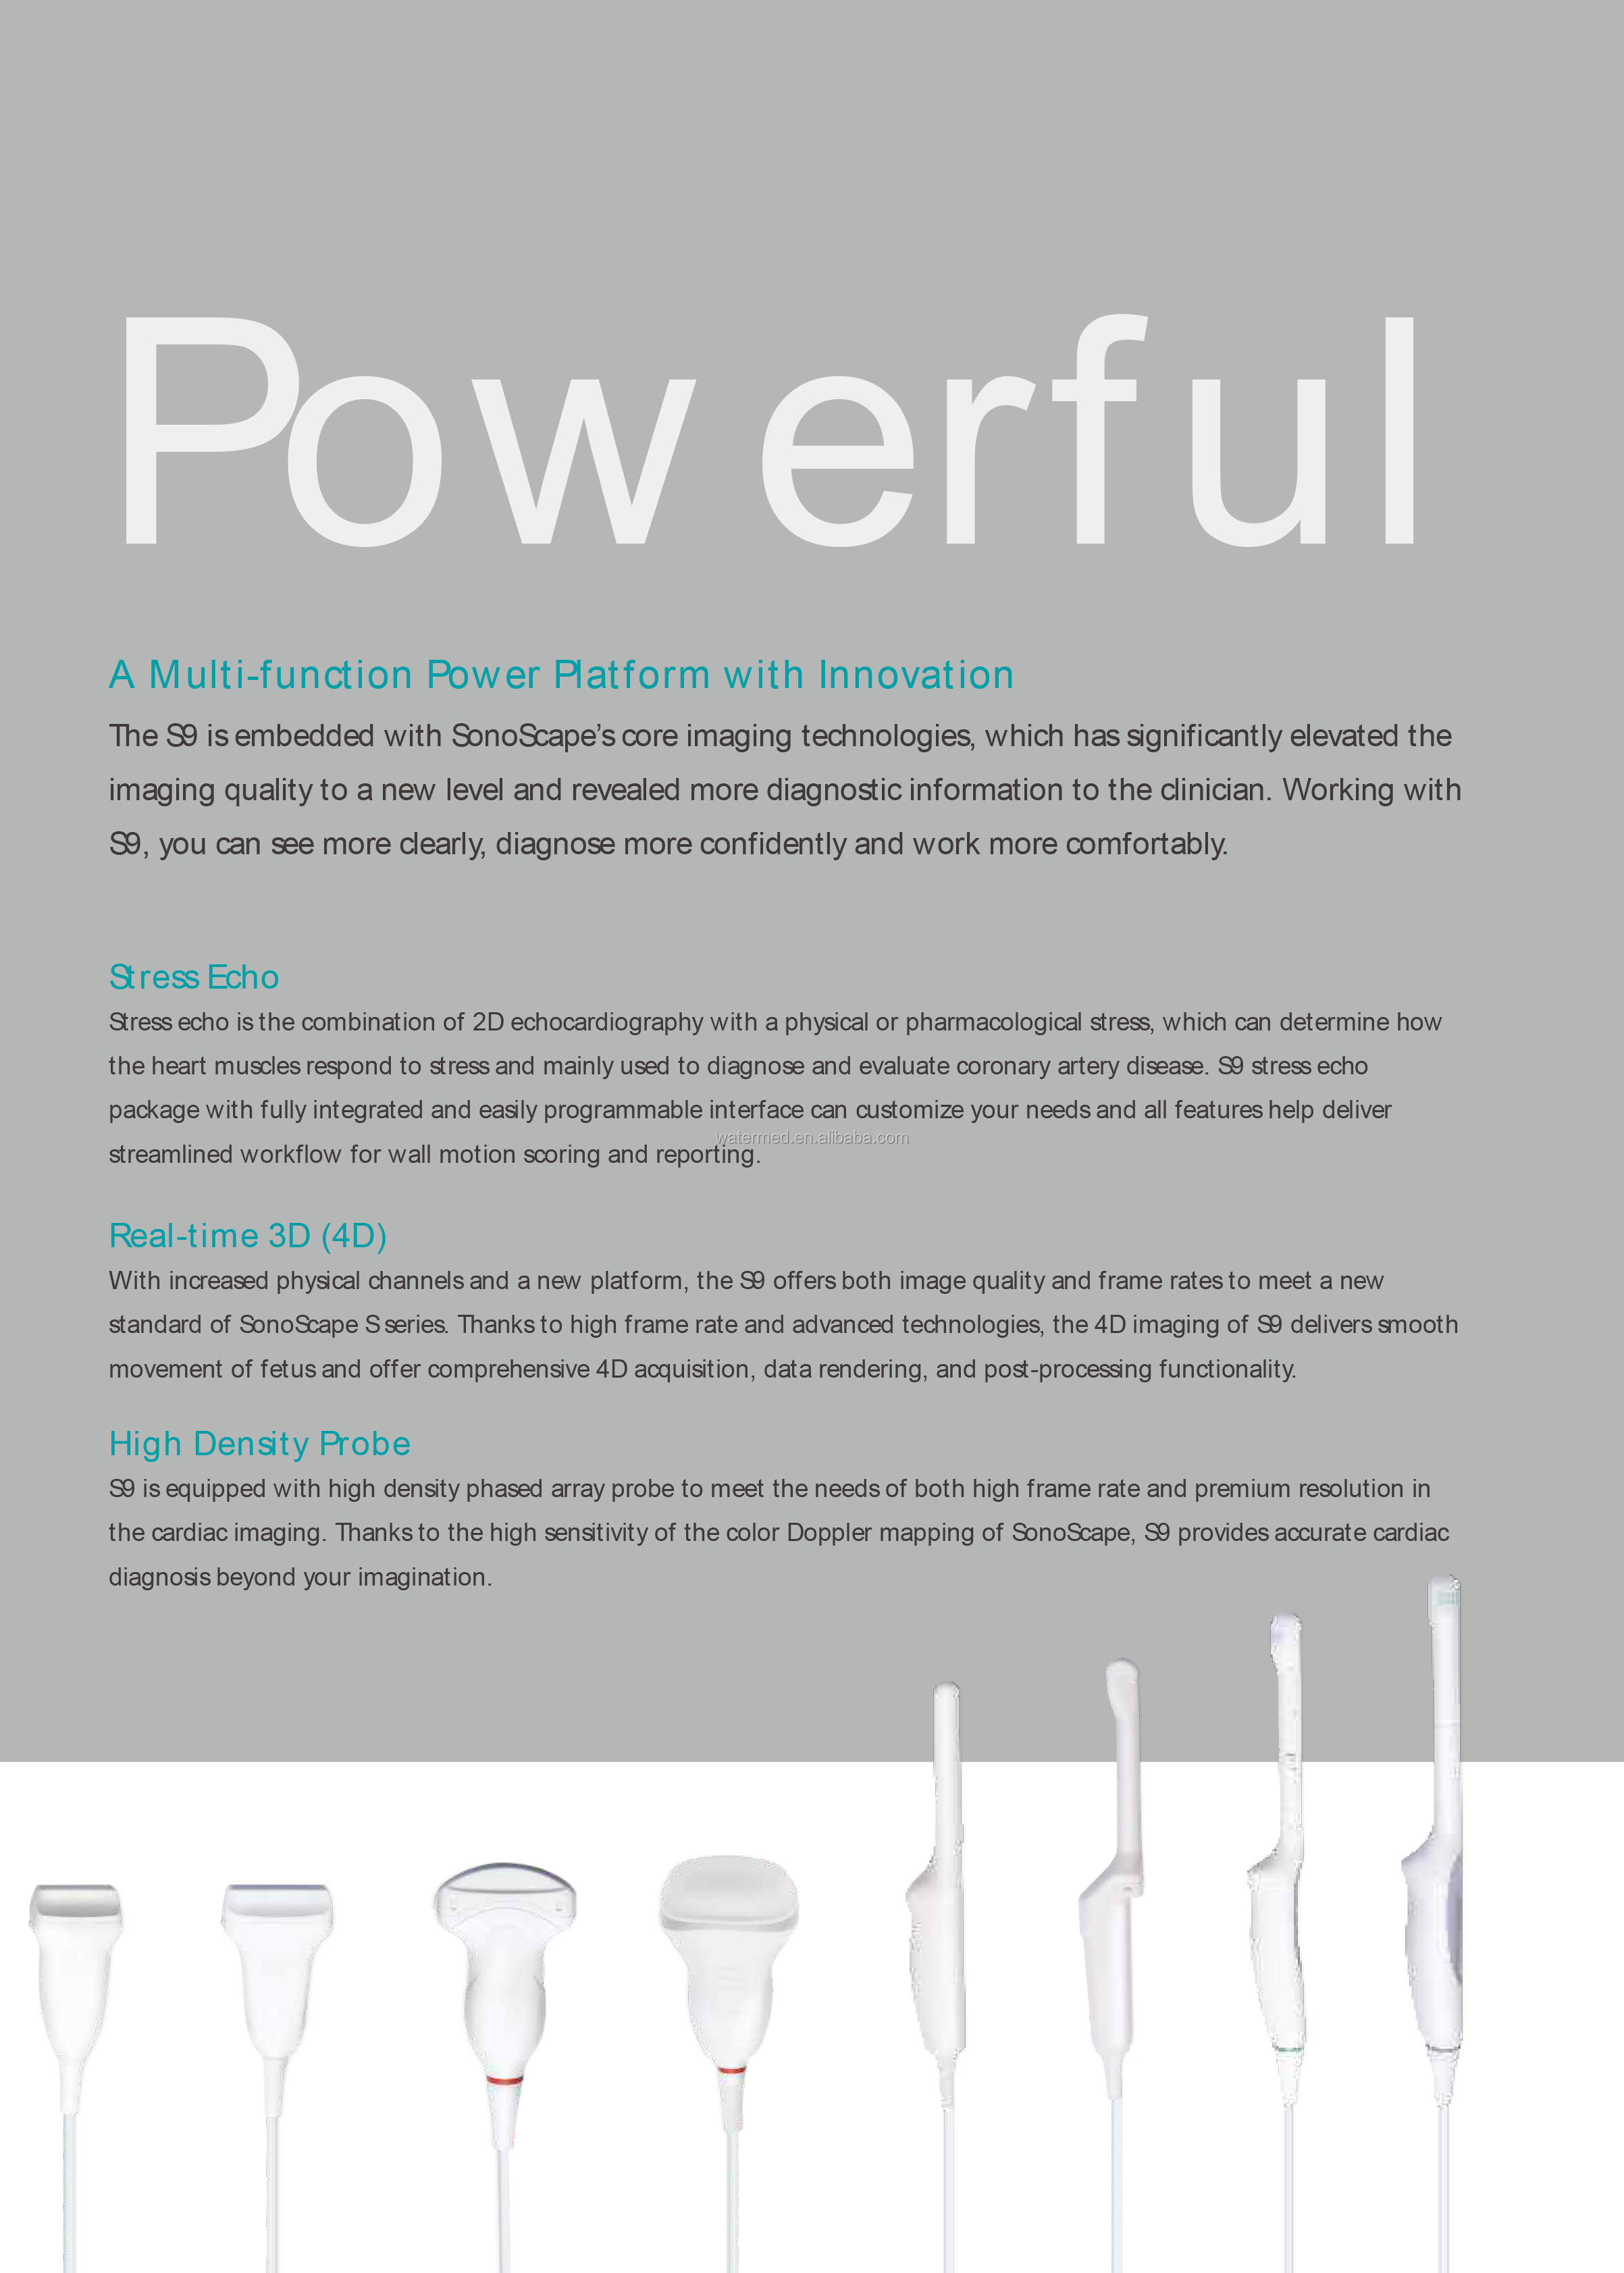

Real-time 3D (4D)

With the addition of physical channels and a new platform, the S9 delivers high-quality imaging and high frame rates to meet the new standard of the SonoScape S series. Thanks to the high frame rate and advanced technology, the S9's 4D imaging can realize the smooth movement of the fetus and provide comprehensive 4D acquisition, data rendering and post-processing functions.

With the addition of physical channels and a new platform, the S9 delivers high-quality imaging and high frame rates to meet the new standard of the SonoScape S series. Thanks to the high frame rate and advanced technology, the S9's 4D imaging can realize the smooth movement of the fetus and provide comprehensive 4D acquisition, data rendering and post-processing functions.

High Density Probe

S9 is equipped with a high-density phased array probe to meet the needs of high frame rate and high resolution for cardiac imaging. Thanks to the high sensitivity of SonoScape color Doppler mapping, the S9 can provide an accurate cardiac diagnosis beyond your imagination.

S9 is equipped with a high-density phased array probe to meet the needs of high frame rate and high resolution for cardiac imaging. Thanks to the high sensitivity of SonoScape color Doppler mapping, the S9 can provide an accurate cardiac diagnosis beyond your imagination.